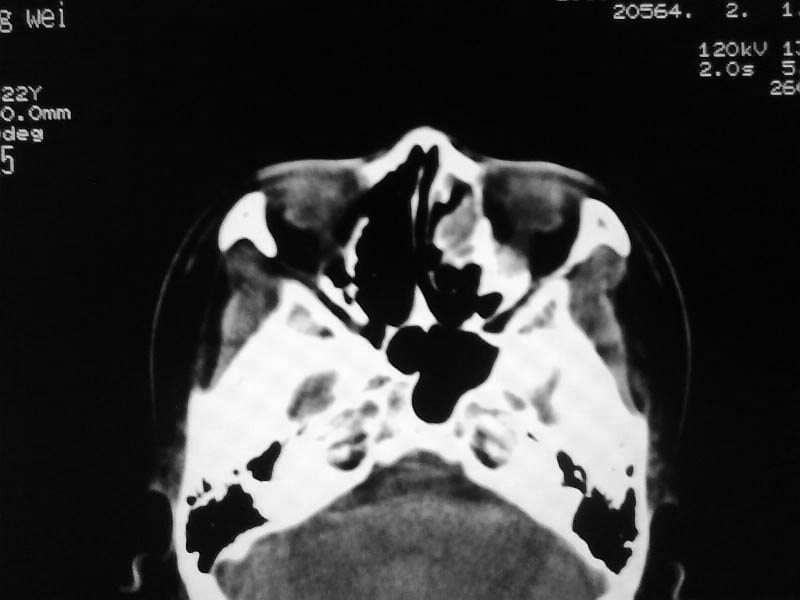

以下是引用zjzjr在2009-5-3 9:59:00的发言:[br]左侧鼻腔息肉、左侧筛窦、上颌窦炎症。双侧下鼻甲粘膜肥厚。

以下是引用随光逐影在2009-5-3 13:02:00的发言:[br]1)左侧鼻腔新生物(息肉可能)。2)左侧上颌窦及左侧筛窦炎症。3)双侧下鼻甲黏膜肥厚。